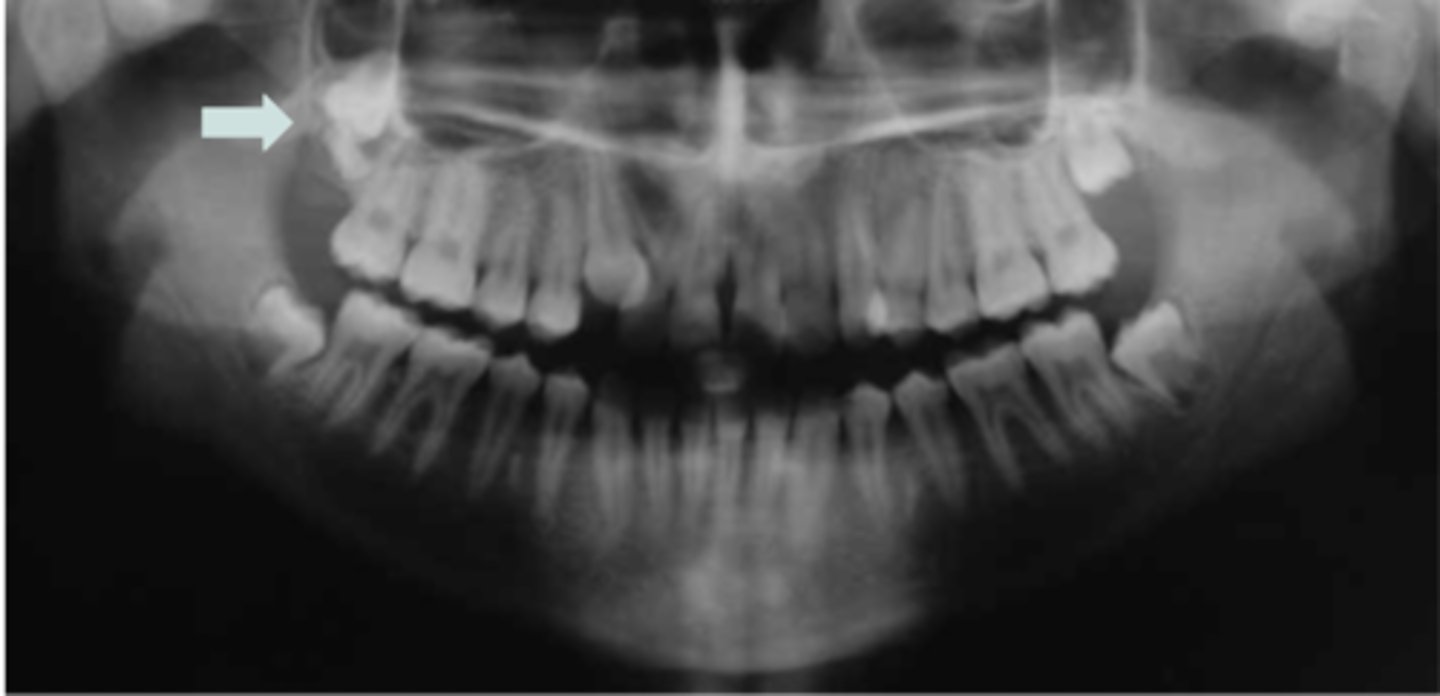

Most common diseases with supernumerary teeth?

Gardner's Syndrome, Cleidocranial Dysplasia

Gardner's Syndrome characteristics?

Supernumerary teeth, osteomas, polyps

Cleidocranial Dysplasia characteristics?

Frontal bossing, missing clavicle